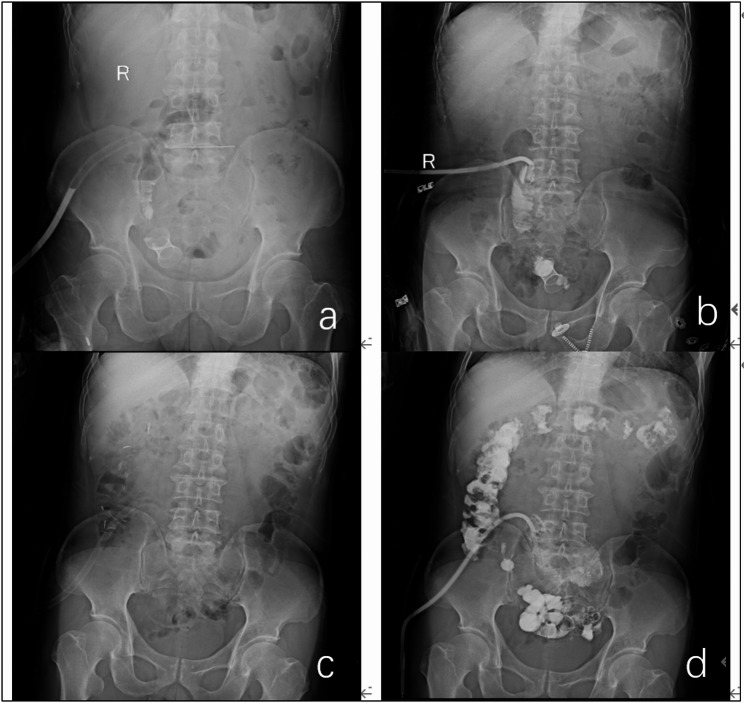

Methods: A retrospective analysis was conducted on 101 patients who underwent laparoscopic radical resection(LAR) for rectal cancer at Yongchuan Hospital from June 2021 to March 2024. Patients were divided into three groups: 26 in the ileum group (using terminal ileal stents) ,54 in the in situ group (using rectal in situ covered stents) and 21 in the control group. Preoperative, surgical, and postoperative data were compared among the three groups.